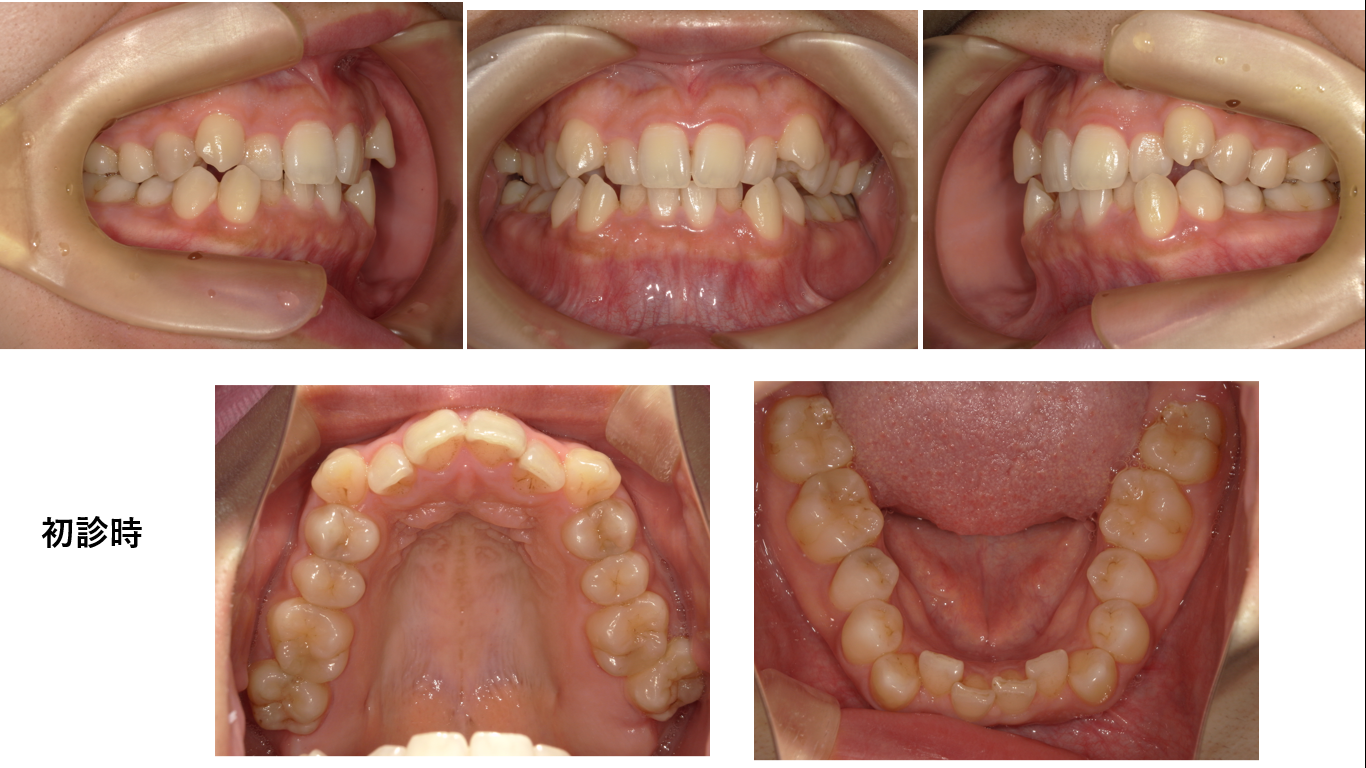

矯正症例137 AngleⅠ級叢生

治療開始年齢:32歳、抜歯部位:上下顎左右4番、治療期間3年6か月、治療費総額¥1,122,000(税込み)

この症例も抜歯が必要な症例です。このような症例にも「マウスピース矯正なら抜歯せず並びます」と言う、とんでもない歯科医師が世の中には存在しますから、矯正をお考えの方は歯科医院選びにはくれぐれも注意してくださいませ。